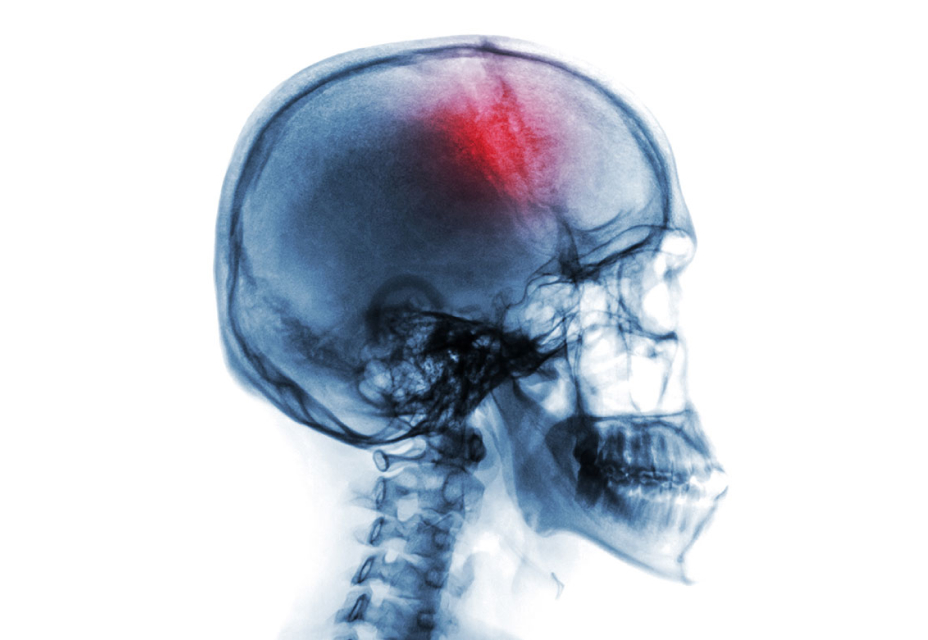

¿Qué hay con el dolor de cabeza? Todos hemos presentado esa molestia que nos impide realizar nuestras actividades diarias. De hecho, es uno de los 10 motivos más frecuentes de consulta médica.1 Pero, ¿cuáles son las diferencias entre un dolor de cabeza “común” y la migraña?

Reconocer los signos de un dolor de cabeza potencialmente peligroso también es crucial. Estos signos incluyen la aparición súbita del dolor intenso, pérdida de la consciencia, dolor de cabeza durante el embarazo, antecedentes de uso de anticoagulantes más dolor de cabeza, traumatismos recientes en la cabeza y persistencia del dolor a pesar del tratamiento. Estos síntomas pueden indicar condiciones que ponen en riesgo la vida y la calidad de vida del paciente, y requieren atención médica inmediata.